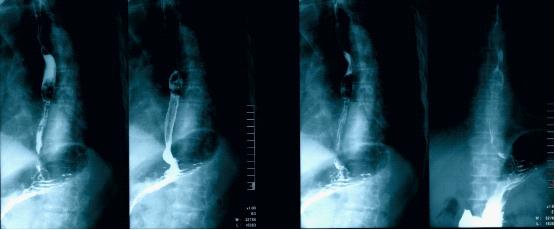

上消化道造影(双重):食管中段类圆形充盈缺损,考虑肿瘤性病变,可能来自食管黏膜下肌层;慢性胃炎;十二指肠升段憩室(图3)

图3